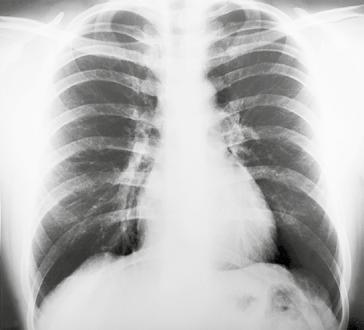

Kromě nakladatelství a výtvarníka se o definitivní podobu třetího dílu učebnice zasloužili mnozí odborníci. Za poskytnutí rtg snímků jsem již od vzniku 1. vydání 3. dílu učebnice vděčný Radiodiagnostické klinice 1. LF UK a paní doc. MUDr. Běle Drugové, DrSc., z radiodiagnostického oddělení Nemocnice Na Homolce. Za vynikající mikrofotografie z vývoje oka děkuji panu prof. MUDr. Františku Vrabcovi, DrSc., který mi je poskytl pro tuto knihu. Panu prof. MUDr. Oldřichu Eliškovi, DrSc., a paní doc. MUDr. Miloslavě Eliškové, CSc., děkuji za poskytnutí podkladů z jejich studií pro vytvoření obrazů mízního odtoku ze srdce. Panu doc. MUDr. Jaromíru Hradcovi, CSc., ze III. interní kliniky 1. LF UK děkuji za poskytnutí echokardiografických obrazů srdce. Upřímně děkuji též oběma spolupracovníkům, panu prof. MUDr. Rastislavu Drugovi, DrSc., a panu prof. MUDr. Miloši Grimovi, DrSc., za porozumění a sympatickou spolupráci na tomto vydání knihy. Studentům, učitelům anatomie i lékařům přeji, aby jim kniha sloužila jako užitečný průvodce a pomocník při studiu tohoto náročného oboru.